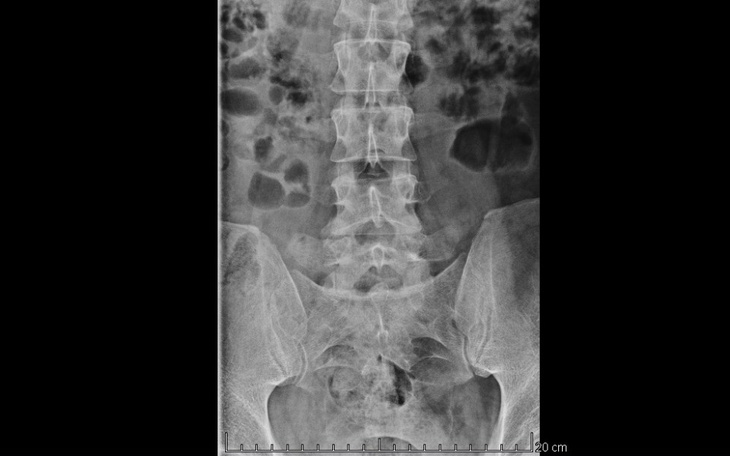

Zdjęcie kręgosłupa, które zamieszczam, jest moje. Opis badania RM oraz sama dokumentacja również należą do mnie.

Opis RM:

Krążki międzykręgowe z początkowymi cechami dehydratacji

Niewielkie okrężne uwypuklenie krążka międzykręgowego L2-L3

Na poziomie L3-L4 rozluźnienie pierścienia włóknistego krążka międzykręgowego

Na poziomie L4-L5 masywna szerokopodstawna centralno lewoboczna protruzja krążka międzykręgowego modelująca worek oponowy i wypełniająca zachyłek boczny lewy z uciskiem korzeni nerwu L5. Wymiar strzałkowy worka oponowego zmniejszony do 4mm

Na poziomie L5-S1 niewielka szerokopodstawna protruzja krążka międzykręgowego z modelowaniem worka oponowego.

Stożek końcowy rdzenia na poziomie L1

Dyskopatia L4-L5 z uciskiem nerwu korzeni L5 po stronie lewej